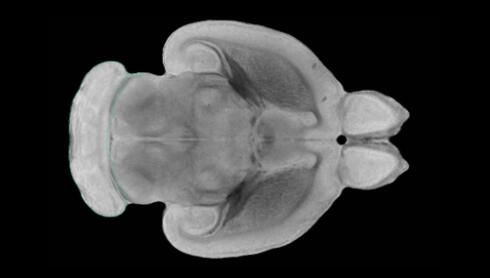

近日,一項(xiàng)刊登在國(guó)際雜志Nature上的研究報(bào)告中,來自劍橋大學(xué)的科學(xué)家們通過研究揭示了隨著年齡增長(zhǎng)大腦僵硬程度的增加導(dǎo)致大腦干細(xì)胞功能異常的分子機(jī)制,同時(shí)研究者還開發(fā)出了一種新方法能將老化的干細(xì)胞逆轉(zhuǎn)回年齡健康狀態(tài);相關(guān)研究結(jié)果有望幫助研究人員理解機(jī)體大腦的老化過程以及如何開發(fā)治療年齡相關(guān)大腦疾病的新型療法。

隨著機(jī)體年齡增加,肌肉和關(guān)節(jié)都會(huì)變得僵硬,這就會(huì)使得日?;顒?dòng)變得更加困難,本文研究表明,我們的大腦也是如此,與年齡相關(guān)的大腦僵硬對(duì)大腦干細(xì)胞的功能或許有著重要影響。文章中,研究人員對(duì)年輕和老化大鼠的大腦進(jìn)行研究闡明了年齡相關(guān)大腦僵硬對(duì)少突膠質(zhì)前體細(xì)胞(OPCs,oligodendrocyte progenitor cells)功能的影響。OPCs是一類對(duì)維持正常大腦功能非常重要的大腦干細(xì)胞,其對(duì)于髓磷脂的再生也非常重要,髓磷脂是神經(jīng)組織周圍的脂肪鞘,在多發(fā)性硬化癥中髓磷脂的再生常常會(huì)被損傷,機(jī)體老化對(duì)這些細(xì)胞的影響常常會(huì)誘發(fā)多發(fā)性硬化癥的發(fā)生,這些細(xì)胞的功能在老化的健康人群中同樣會(huì)下降。

為了確定老化OPCs的功能缺失是否可以被逆轉(zhuǎn),研究人員將來自老化大鼠機(jī)體的老化OPCs轉(zhuǎn)移到了年輕大鼠柔軟的海綿狀大腦組織中去,值得注意的是,這些老化的大腦細(xì)胞能夠重新恢復(fù)活力,其行為非常像年輕更加強(qiáng)壯的細(xì)胞。這項(xiàng)研究中,研究人員在實(shí)驗(yàn)室中開發(fā)出了具有可變僵硬程度的新型材料,并在受控環(huán)境下研究這些材料的生長(zhǎng)及其對(duì)大鼠大腦干細(xì)胞的影響,這些材料能被工程化改造具有和年齡或老化大腦相似的柔軟程度。

為了深入理解大腦組織柔軟和僵硬影響細(xì)胞行為的分子機(jī)制,研究人員對(duì)細(xì)胞表面一種名為Piezo1的蛋白質(zhì)進(jìn)行了分析,該蛋白質(zhì)能“告知”細(xì)胞其周圍的環(huán)境為柔軟或僵硬。研究者Kevin Chalut說道,我們發(fā)現(xiàn),當(dāng)在僵硬材料上促進(jìn)年輕具有功能性的大鼠干細(xì)胞時(shí),這些細(xì)胞就會(huì)表現(xiàn)出功能異常,并失去其再生的能力,實(shí)際上其行為與老化細(xì)胞相似。當(dāng)將老化的大腦細(xì)胞在柔軟材料上生長(zhǎng)時(shí),其功能就會(huì)表現(xiàn)得像年輕細(xì)胞一樣,換句話說,其能夠重新恢復(fù)年輕的活力。

當(dāng)研究者從老化大腦干細(xì)胞的表面剔除Piezo1蛋白后,他們就能夠誘騙細(xì)胞感知柔軟的周圍環(huán)境,甚至當(dāng)將細(xì)胞在僵硬材料上生長(zhǎng)時(shí)也是如此。此外,當(dāng)在老化大鼠大腦中剔除OPCs上的Piezo1時(shí),就會(huì)促進(jìn)細(xì)胞變得年輕并再次承擔(dān)正常的再生功能。研究者Susan Kohlhaas表示,多發(fā)性硬化癥是一種痛苦讓患者致殘的疾病,隨著時(shí)間推移,我們迫切需要開發(fā)出減緩并抑制患者殘疾的新型療法。這項(xiàng)研究中,研究人員闡明了大腦干細(xì)胞老化的分子機(jī)制,以及如何通過逆轉(zhuǎn)該過程來實(shí)現(xiàn)恢復(fù)大腦干細(xì)胞活力,后期研究人員將會(huì)基于本文研究開發(fā)出新型療法來治療多種與老化和多發(fā)性硬化癥相關(guān)的疾病,包括如何潛在恢復(fù)大腦失去的功能等。